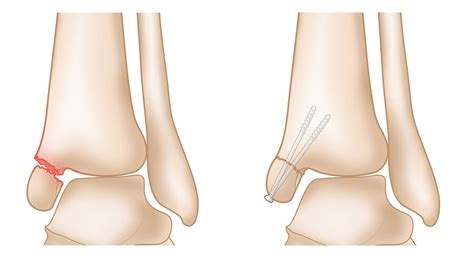

For more severe fractures, surgery may be necessary to realign the bones and stabilize the joint. Surgical options include:

• Open Reduction and Internal Fixation (ORIF): Involves making an incision to realign the bones and using plates, screws, or rods to hold them in place.

• Arthroscopy: A minimally invasive procedure using a small camera to visualize and repair the joint.